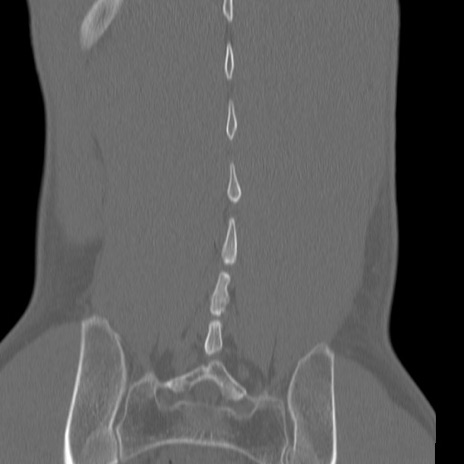

腰椎CT

3D再構成